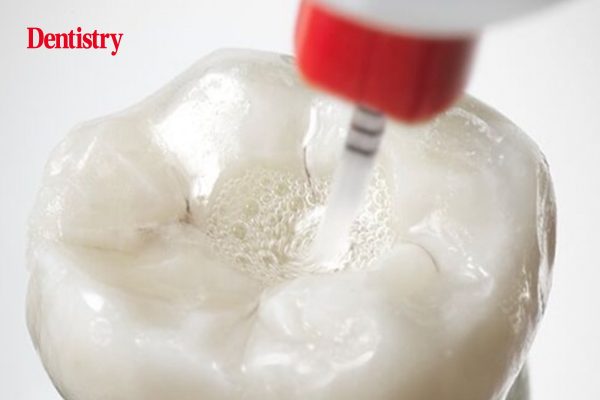

KometBioSeal – the new bioceramic root filling sealer

KometBioSeal is a new root filling sealer from Komet Dental that creates the perfect bond between filling material and root…